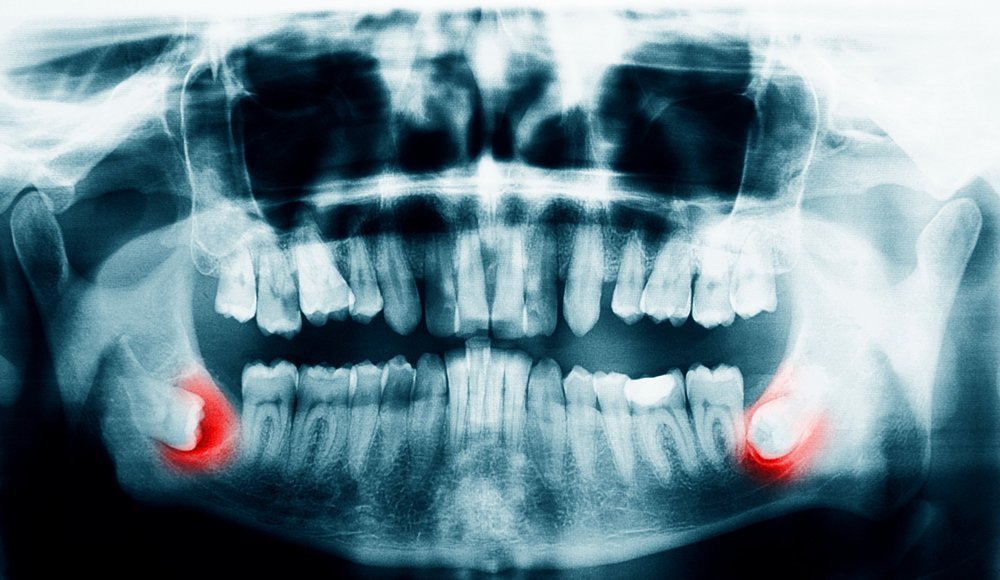

Fourth week of braces, on my third day post extraction (had 4 teeth